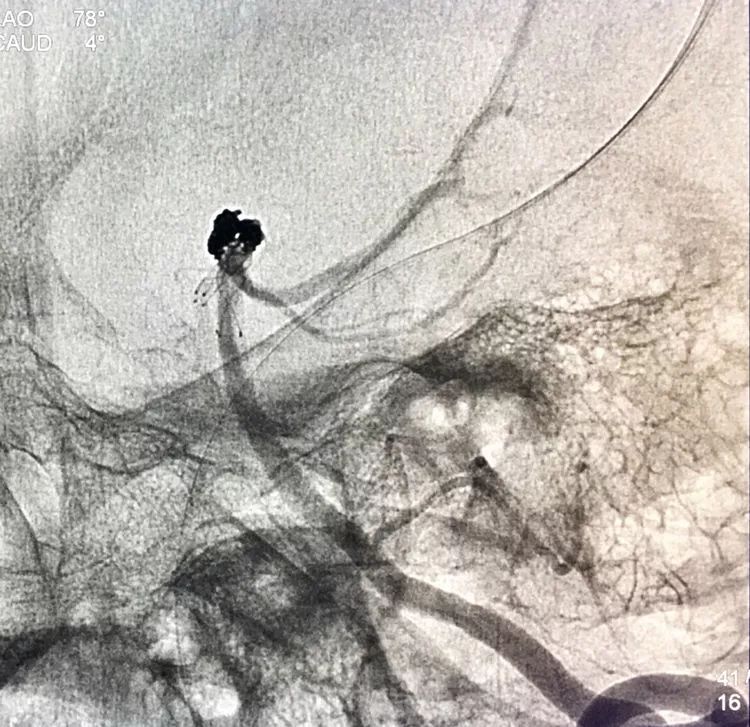

左椎动脉工作位路图

Sychro14微导丝携Headway21支架导管经左椎动脉-基底动脉进入右侧PCA,因瘤颈主要累及右侧PCA,故计划支架跨基底动脉顶端动脉瘤释放于右侧PCA-基底动脉内。

Echelon10(直头)微导管用Sychro14微导丝引入瘤腔内。

先送入一段弹簧圈

将LVIS支架(3.5×15)跨瘤颈释放于右侧PCA-基底动脉内

在支架保护下输送弹簧圈栓塞瘤腔

此时从工作位(右斜17°反汤9°)看弹簧圈分布致密,微导管头已被顶到瘤颈处

工作位造影看动脉瘤栓塞满意,子瘤已不显影,是不是可以收手了呢?

旋转增强器透视观察各个投照角度弹簧圈的分布情况,侧位透视发现瘤腔后部的弹簧圈分布疏松,形成死腔,看来革命还未成功,同志尚需努力呀!